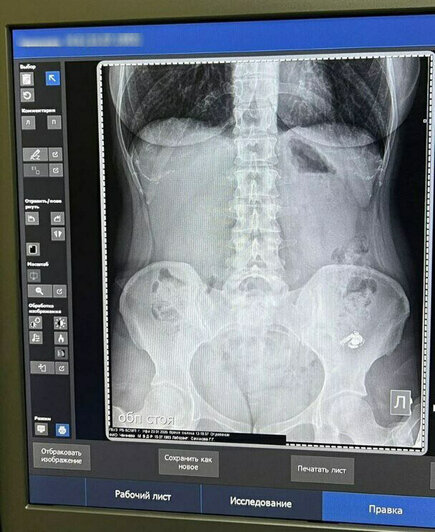

Повторный снимок, к счастью, подтвердил, что всё идёт как надо, инородный предмет постепенно опускается ниже по ЖКТ. Ей рекомендовали мягкую диету для улучшения перистальтики кишечника и отправили ждать дальше. Наконец, поздно вечером на вторые сутки проблема благополучно разрешилась.

На первом снимке наушник левее: в кадр кроме него случайно попало украшение на теле. Фото: Мария